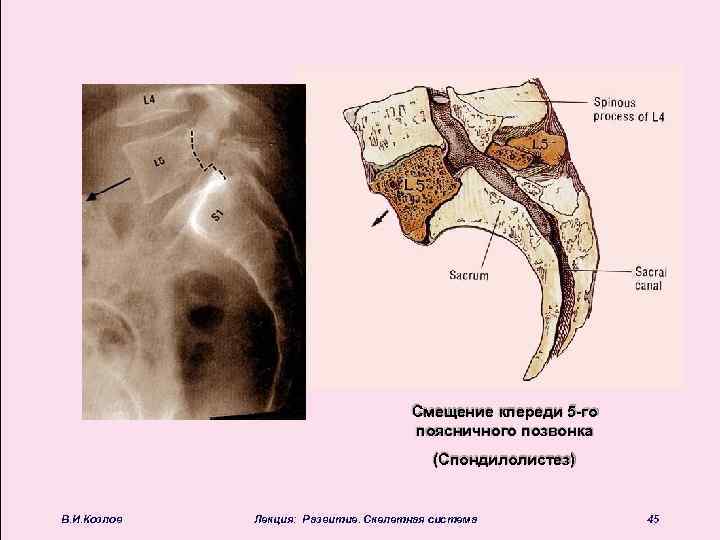

Смещение кпереди 5 -го поясничного позвонка (Спондилолистез) В. И. Козлов Лекция: Развитие. Скелетная система 45